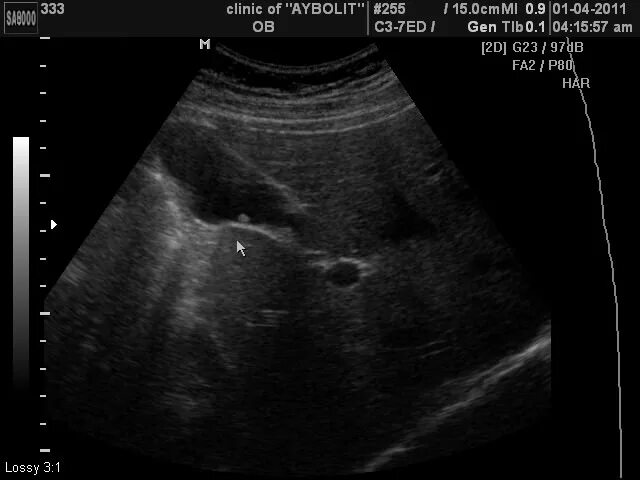

Перегиб тела и шейки желчного пузыря